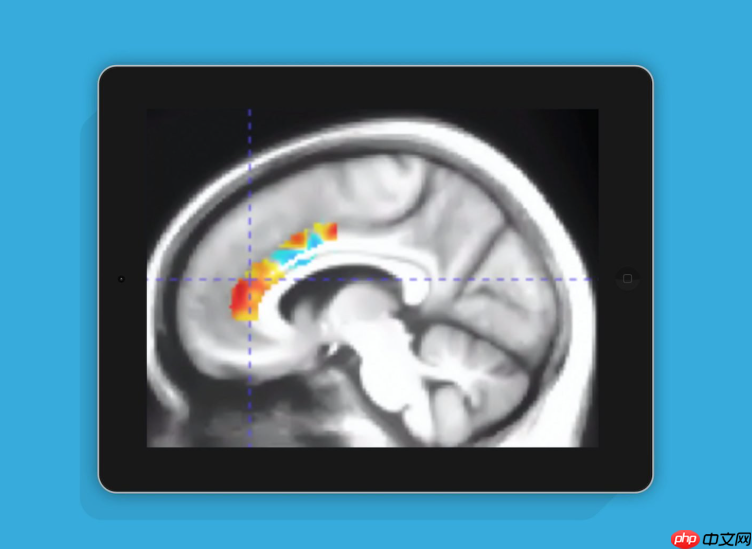

如今,玩游戏早已不再被视为荒废学业或事业的“头号敌人”。根据美国研究机构最新发布的一项调查成果显示,老年人只要坚持玩10周的大脑训练类游戏,其认知功能的改善效果相当于逆转了10年的脑部老化进程。

这项研究由美国Posit Science Corporation公司的Mouna Attarha领衔团队完成,并发表了一篇题为《Effects of Computerized Cognitive Training on Vesicular Acetylcholine Transporter Levels using [18F]Fluoroethoxybenzovesamicol Positron Emission Tomography in Healthy Older Adults: Results from the Improving Neurological Health in Aging via Neuroplasticity-based Computerized Exercise (INHANCE) Randomized Clinical Trial([18F]》的论文。该研究系统探讨了计算机化认知训练游戏对大脑退化相关神经指标的影响。

研究共招募了92名年长参与者,平均年龄为71.9岁,平均接受教育年限达16.5年。经过持续数月的实验干预,结果显示:连续进行10周特定大脑训练游戏的老年人,在认知功能方面表现出显著提升,其大脑功能状态相当于年轻了十年。